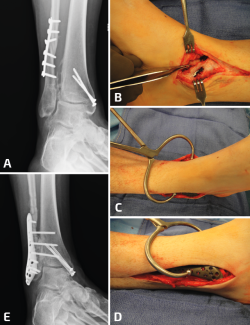

Se puede recurrir a la osteotomía de la tibia para corregir la deformidad en valgo del pilón. Esto se puede realizar mediante una cuña de sustracción interna o una cuña de adición externa de la tibia (Figura 6). En este caso, la consolidación viciosa oblicua del peroné facilitará la osteotomía oblicua del mismo para lograr una buena elongación y en este caso no se utilizaría injerto óseo(11).

Figura 6. En un caso donde el plafón tibial se encuentra en valgo, solo elongar el peroné no será suficiente. Observen el pie plano como resultado del tobillo y el retropié en valgo (A, B). Se realizaron conjuntamente una elongación del peroné, una osteotomía en cuña de cierre con base medial de la tibia y una osteotomía medializadora del calcáneo. Observen una mejoría en la alineación, pero la persistencia de un leve valgo de tobillo (C, D).

Debido a la deformidad en valgo del tobillo y la artritis precoz, se debe realizar una osteotomía simultánea de la tibia para alinear las fuerzas de carga sobre el tobillo, ya que solo con la elongación del peroné no es suficiente. Los tejidos que rodean el peroné podrían necesitar desbridarse elevando el periostio por completo y luego se moviliza el peroné sobre su pedículo distal (Figura 7).

Figura 7. En este caso, además de una deformidad en valgo del plafón, se agrega una pseudoartrosis del peroné con acortamiento del mismo y un ensanchamiento de la sindesmosis. Solo se ve la mitad lateral del plafón impactada en valgo, por lo que una osteotomía en cuña de cierre con base medial de la tibia no es necesaria (A, B). Se desbrida la sindesmosis y se retrae el peroné hacia lateral (C), se elonga y se realiza una osteotomía intraarticular (plafonplastia) del borde lateral de la tibia (descrita por Myerson) (D). La tibia lateral se distrae gradualmente hasta observar la posición neutra del pilón (E); se coloca injerto óseo y se estabiliza la sindesmosis (F).

Figura 8. Generalmente, las deformidades en valgo del plafón tibial se acompañan con deformidades severas del peroné; sin embargo, a veces pueden ser consecuencia de una fractura de Weber B (A, B). En este caso, la gotera interna se limpió por artroscopia, se elongó el peroné, pero todavía hacía falta una osteotomía de cierre de base medial (C).

Otra variante de una consolidación viciosa del peroné se asocia con la compresión del pilón externo y la inclinación en valgo de la mortaja del tobillo. Como se describió más arriba, estos casos deben tratarse mediante osteotomía del peroné, además de una osteotomía en cuña de sustracción de la cara interna de la tibia para la realineación del tobillo (Figuras 8 y 9).

Figura 9. Las consolidaciones viciosas o pseudoartrosis del peroné pueden producirse en el contexto de una fractura de estrés. En este paciente, una fractura por estrés tras una triple artrodesis indica una deformidad en valgo (A, B). A pesar de elongar 1 cm el peroné, se debe realizar una osteotomía de cierre lateral de la tibia distal (C, D).